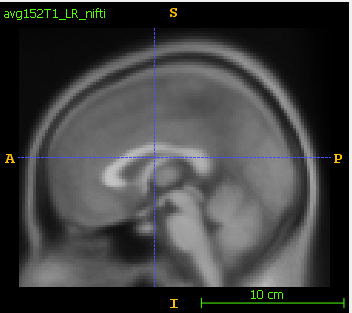

- Open in itk-snap/slicer the original nifti and then the dicom. The dicom is flipped up-down.

- In itk-snap, the original nifti is:

The saved dicom is flipped in S-I axis: